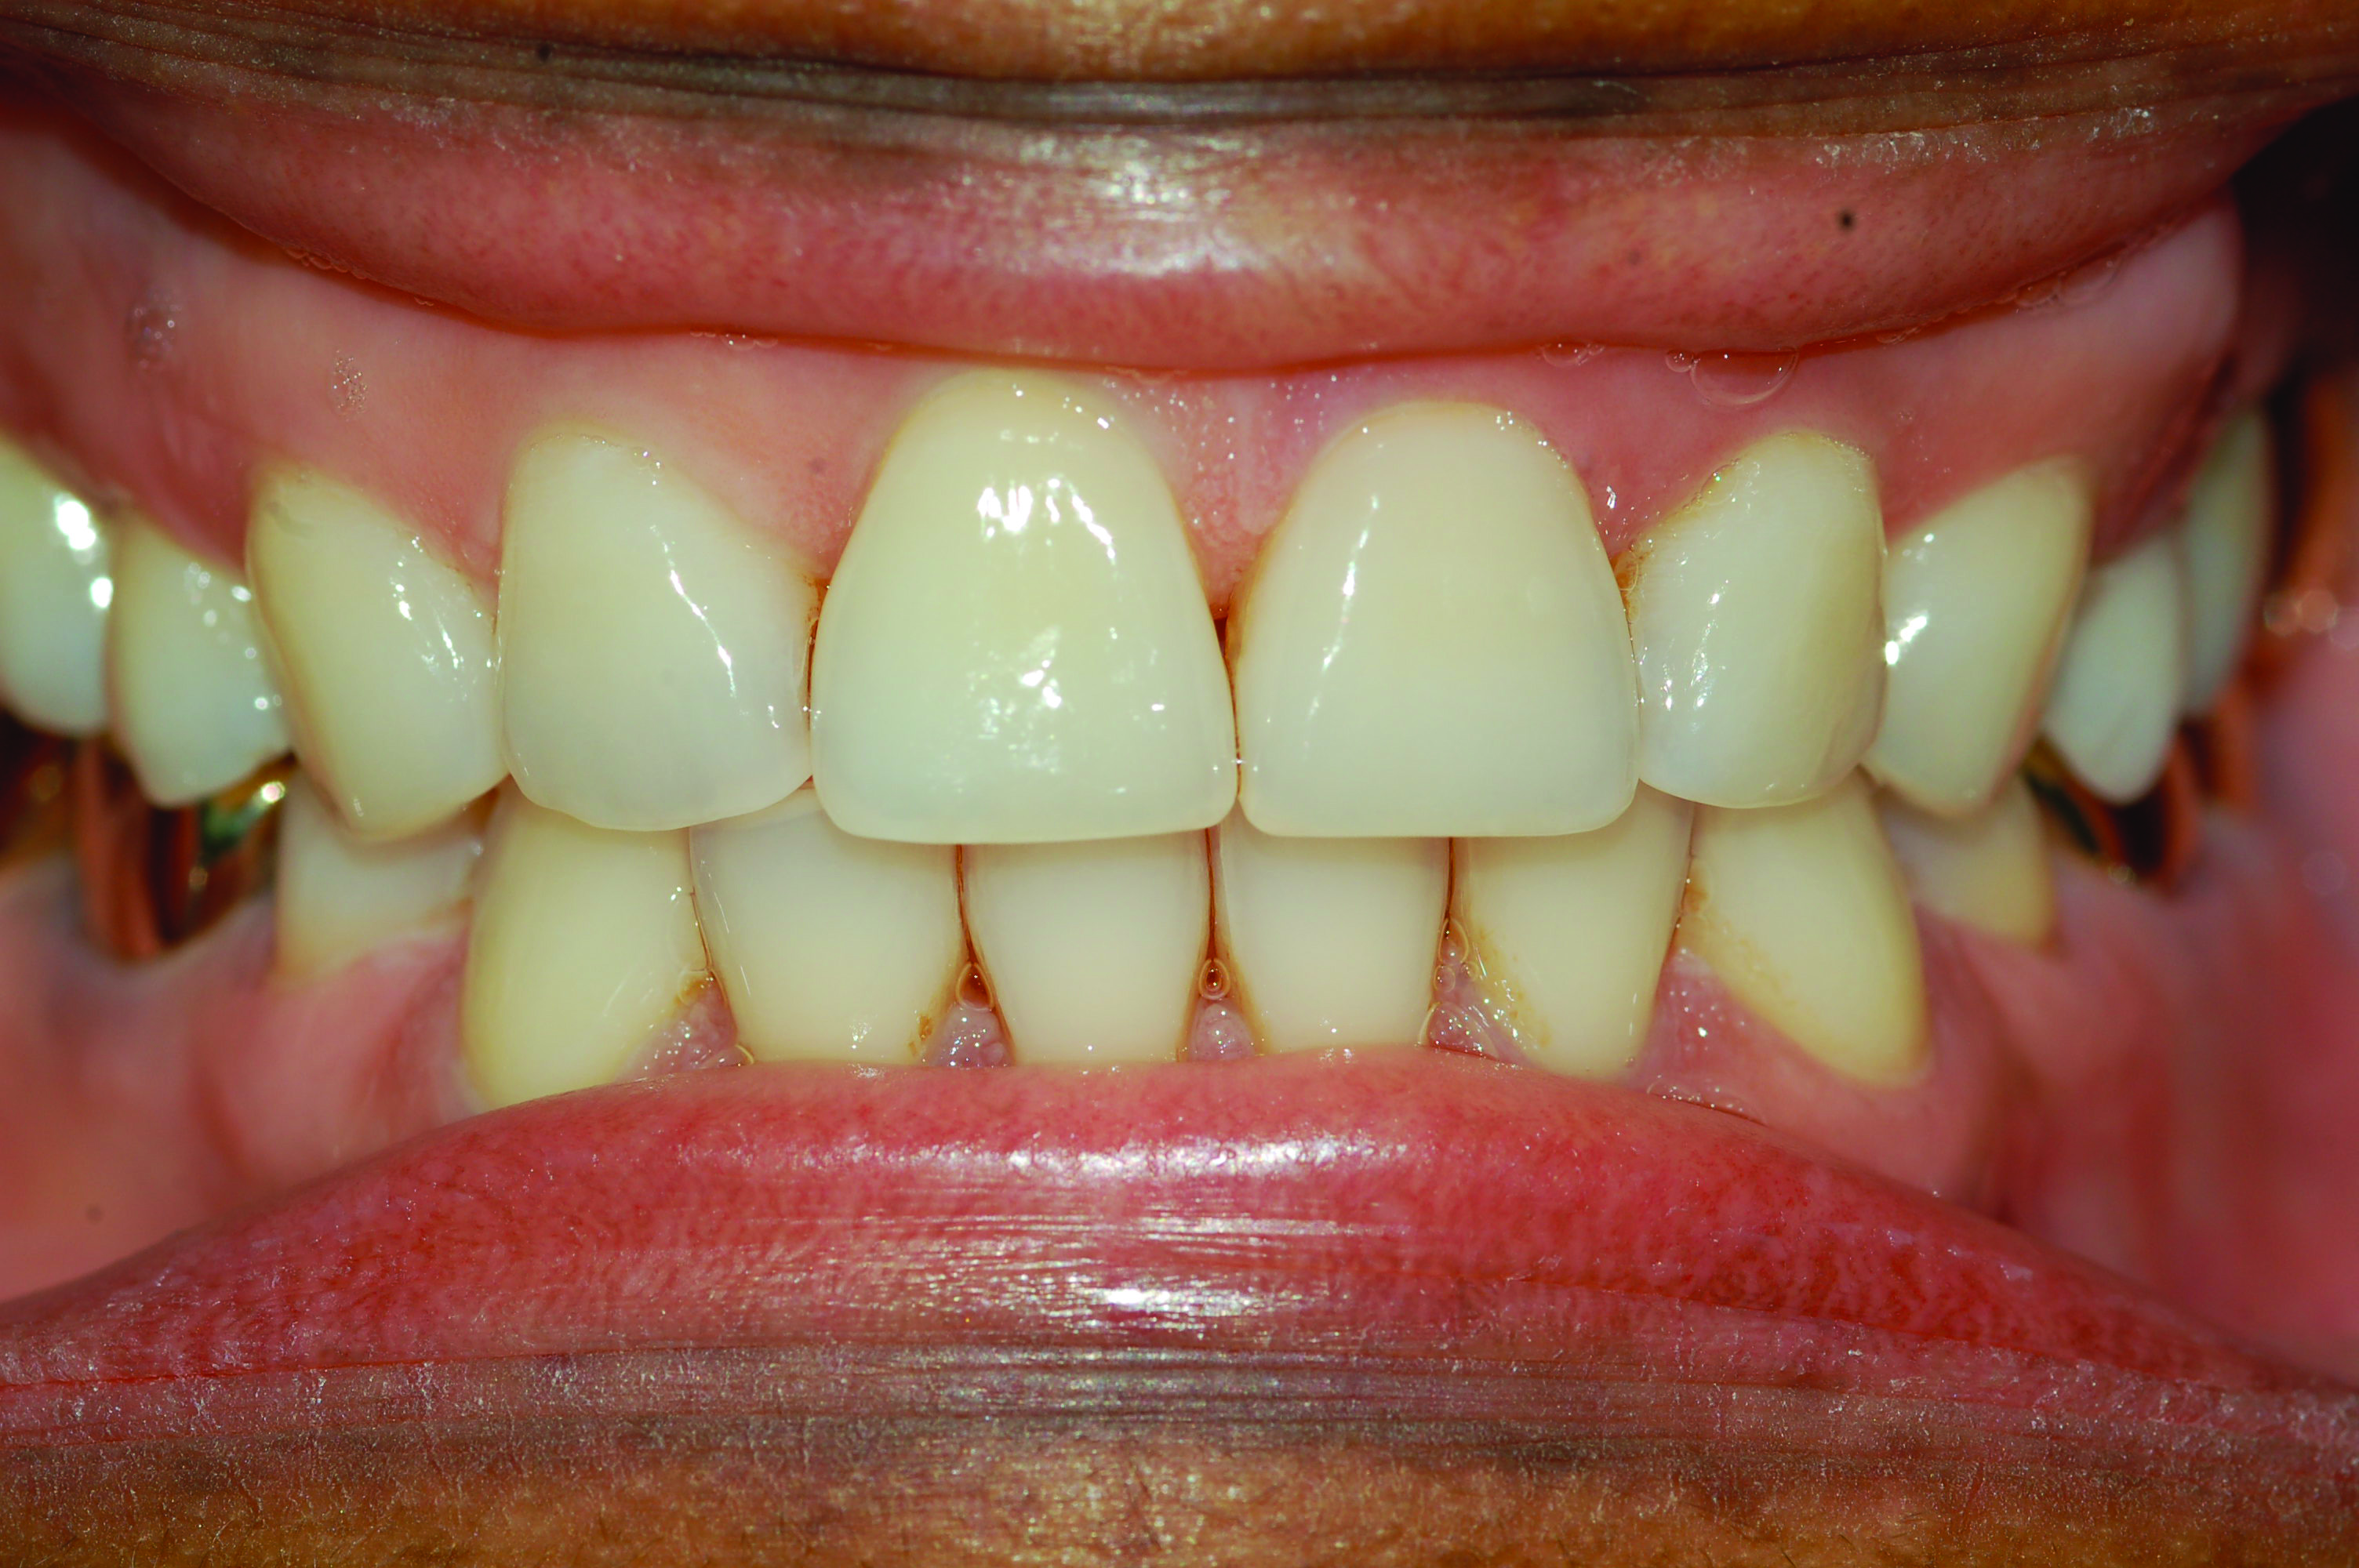

Fig 7. Development of posterior open bite. Photograph of male patient with teeth maximally intercuspated prior to treatment (AHI in supine position = 88.2 events/hr).

Figure 7

Fig 8. Photograph of teeth maximally intercuspated 10 months after patient began treatment with a MAD (TAP® appliance). With the jaw advanced 95% of maximum protrusion, the AHI in the supine position was reduced to 1.1 events/hr. A posterior open bite was observed on both sides of the dental arch.

Figure 8

Within the first few months of treatment, some patients report difficulty achieving a firm bite with the back teeth. The mechanism underlying the development of this posterior open bite is unclear but of intense interest. When observed early after the beginning of treatment, it may be due to changes in the TMJ soft tissue or in the masticatory muscles. Later in treatment, the development of a posterior open bite may reflect the inability to fully close due to premature contact of the anterior teeth (Figure 7 and Figure 8).11 Alternatively, some investigators have suggested an anterior bony repositioning of the mandible from its original position.12